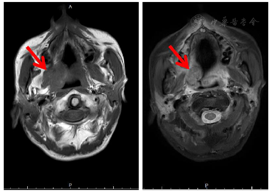

软腭偏右侧及口咽右侧壁见增多软组织影,范围约2.6 cm×2.7 cm,增强明显不均匀强化,周围见压脂高信号;口咽右侧壁、扁桃体区见斑片状异常信号影,边界不清,T1W呈等信号、T2W呈稍高信号,T2W压脂呈高信号,其内信号欠均匀,增强扫描明显强化,周围脂肪间隙稍肿胀,病灶与右侧颈部血管分界清晰,未见明显受累征象。鼻咽壁未见明显增厚,双侧咽隐窝对称。双侧声带未见明显增厚;甲状腺不大,其实质信号未见确切异常。双侧颈部未见明显肿大淋巴结影。扫及区骨质未见明显吸收破坏(图2)。